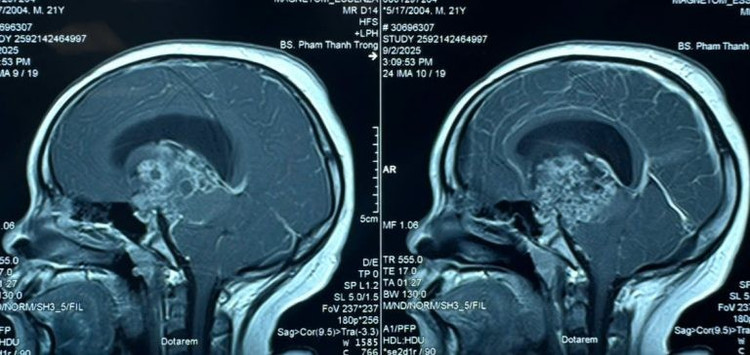

Kết quả cho thấy, anh S. có khối u não lớn kích thước 6cm, khối u nằm ở vị trí giữa não gây chèn ép dẫn đến hiện tượng giãn não thất, làm dịch não tủy không thể lưu thông – nguyên nhân khiến người bệnh rơi vào hôn mê.

Hình ảnh MRI khối u sọ hầu - Ảnh BVCC